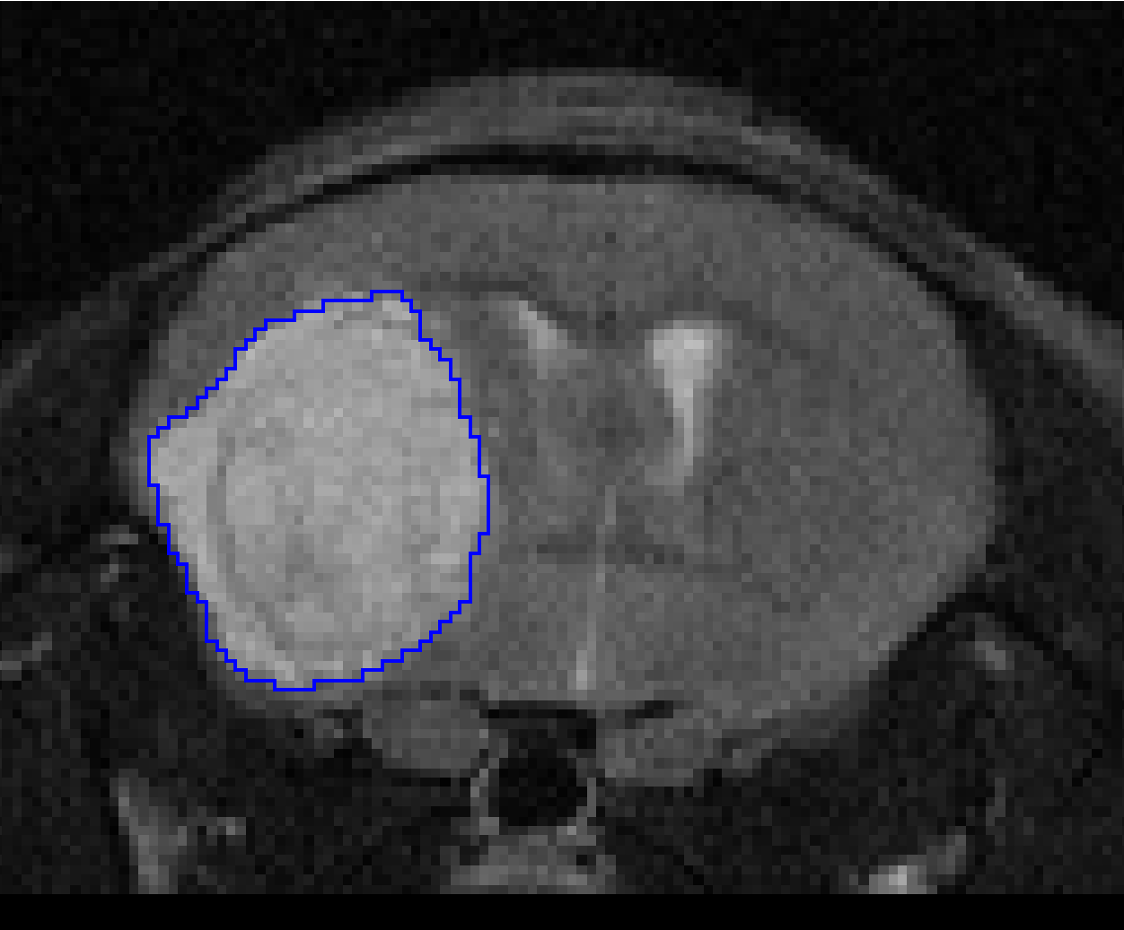

pmod’s tools provide comprehensive workflows for post-processing and quantification of imaging data for fundamental oncology research, development of radiotracers and theranostics, and in clinical research studies. Imaging scientists can trust pmod to reproducibly read their data, interpret the meta-data/units and help users calculate statistics such as SUV for their studies and publications.

• Multimodality segmentation tools – comprehensive semi-automated and manual tools for precision and reproducibility